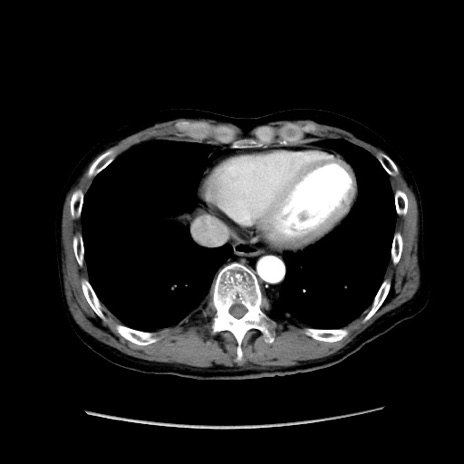

症例37(横断像)

【症例】40歳代 男性

【主訴】腹痛

【現病歴】4時間ほど前に電車に乗車中に臍部上より腹痛出現。徐々に増悪し起立困難となり、救急外来受診。生ものは数日食べていない。今朝お雑煮を食べた。

【身体所見】BT 36.8℃、BP 117/84mmHg、HR 91/min、SpO2 97%、苦悶様、腹部:臍上部広範囲圧痛あり、反跳痛±

【データ】WBC 8100、CRP 0.03